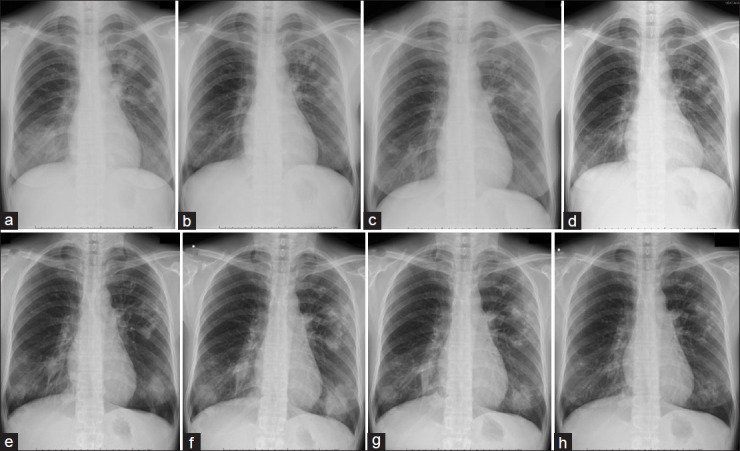

A 32-year-old Chinese woman with a cough and bloody sputum was diagnosed with chronic eosinophilic pneumonia. After starting corticosteroid therapy, chest radiography showed improvement in the bilateral infiltrative shadow. However, chest image findings showed worsening of the bilateral infiltrative shadow and pulmonary cavities during the 20 mg/day of oral prednisolone therapy. Transbronchial lung biopsy and bronchoalveolar lavage were repeated, and the patient was diagnosed with pulmonary paragonimiasis. After starting praziquantel treatment, chest radiography findings and clinical symptoms improved. Careful follow-up during corticosteroid therapy is important to judge whether transient improvement and true deterioration of radiological findings.

一名32岁中国女性因咳嗽和痰血被诊断为慢性嗜酸性粒细胞性肺炎。开始皮质类固醇治疗后,胸片显示双侧浸润影改善。然而,在口服强的松龙20mg /d治疗期间,胸部图像显示双侧浸润阴影和肺腔恶化。经支气管肺活检及支气管肺泡灌洗,诊断为肺吸虫病。开始吡喹酮治疗后,胸片表现和临床症状均有所改善。在皮质类固醇治疗期间的仔细随访对于判断放射学表现是否有短暂改善和真正恶化是很重要的。